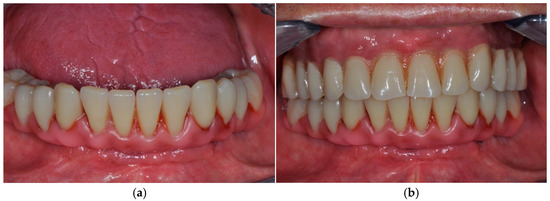

The Effectiveness and Predictability of BioHPP (Biocompatible High-Performance Polymer) Superstructures in Toronto-Branemark Implant-Prosthetic Rehabilitations: A Case Report

3. Case Presentation